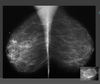

types of breast caner

111

classification